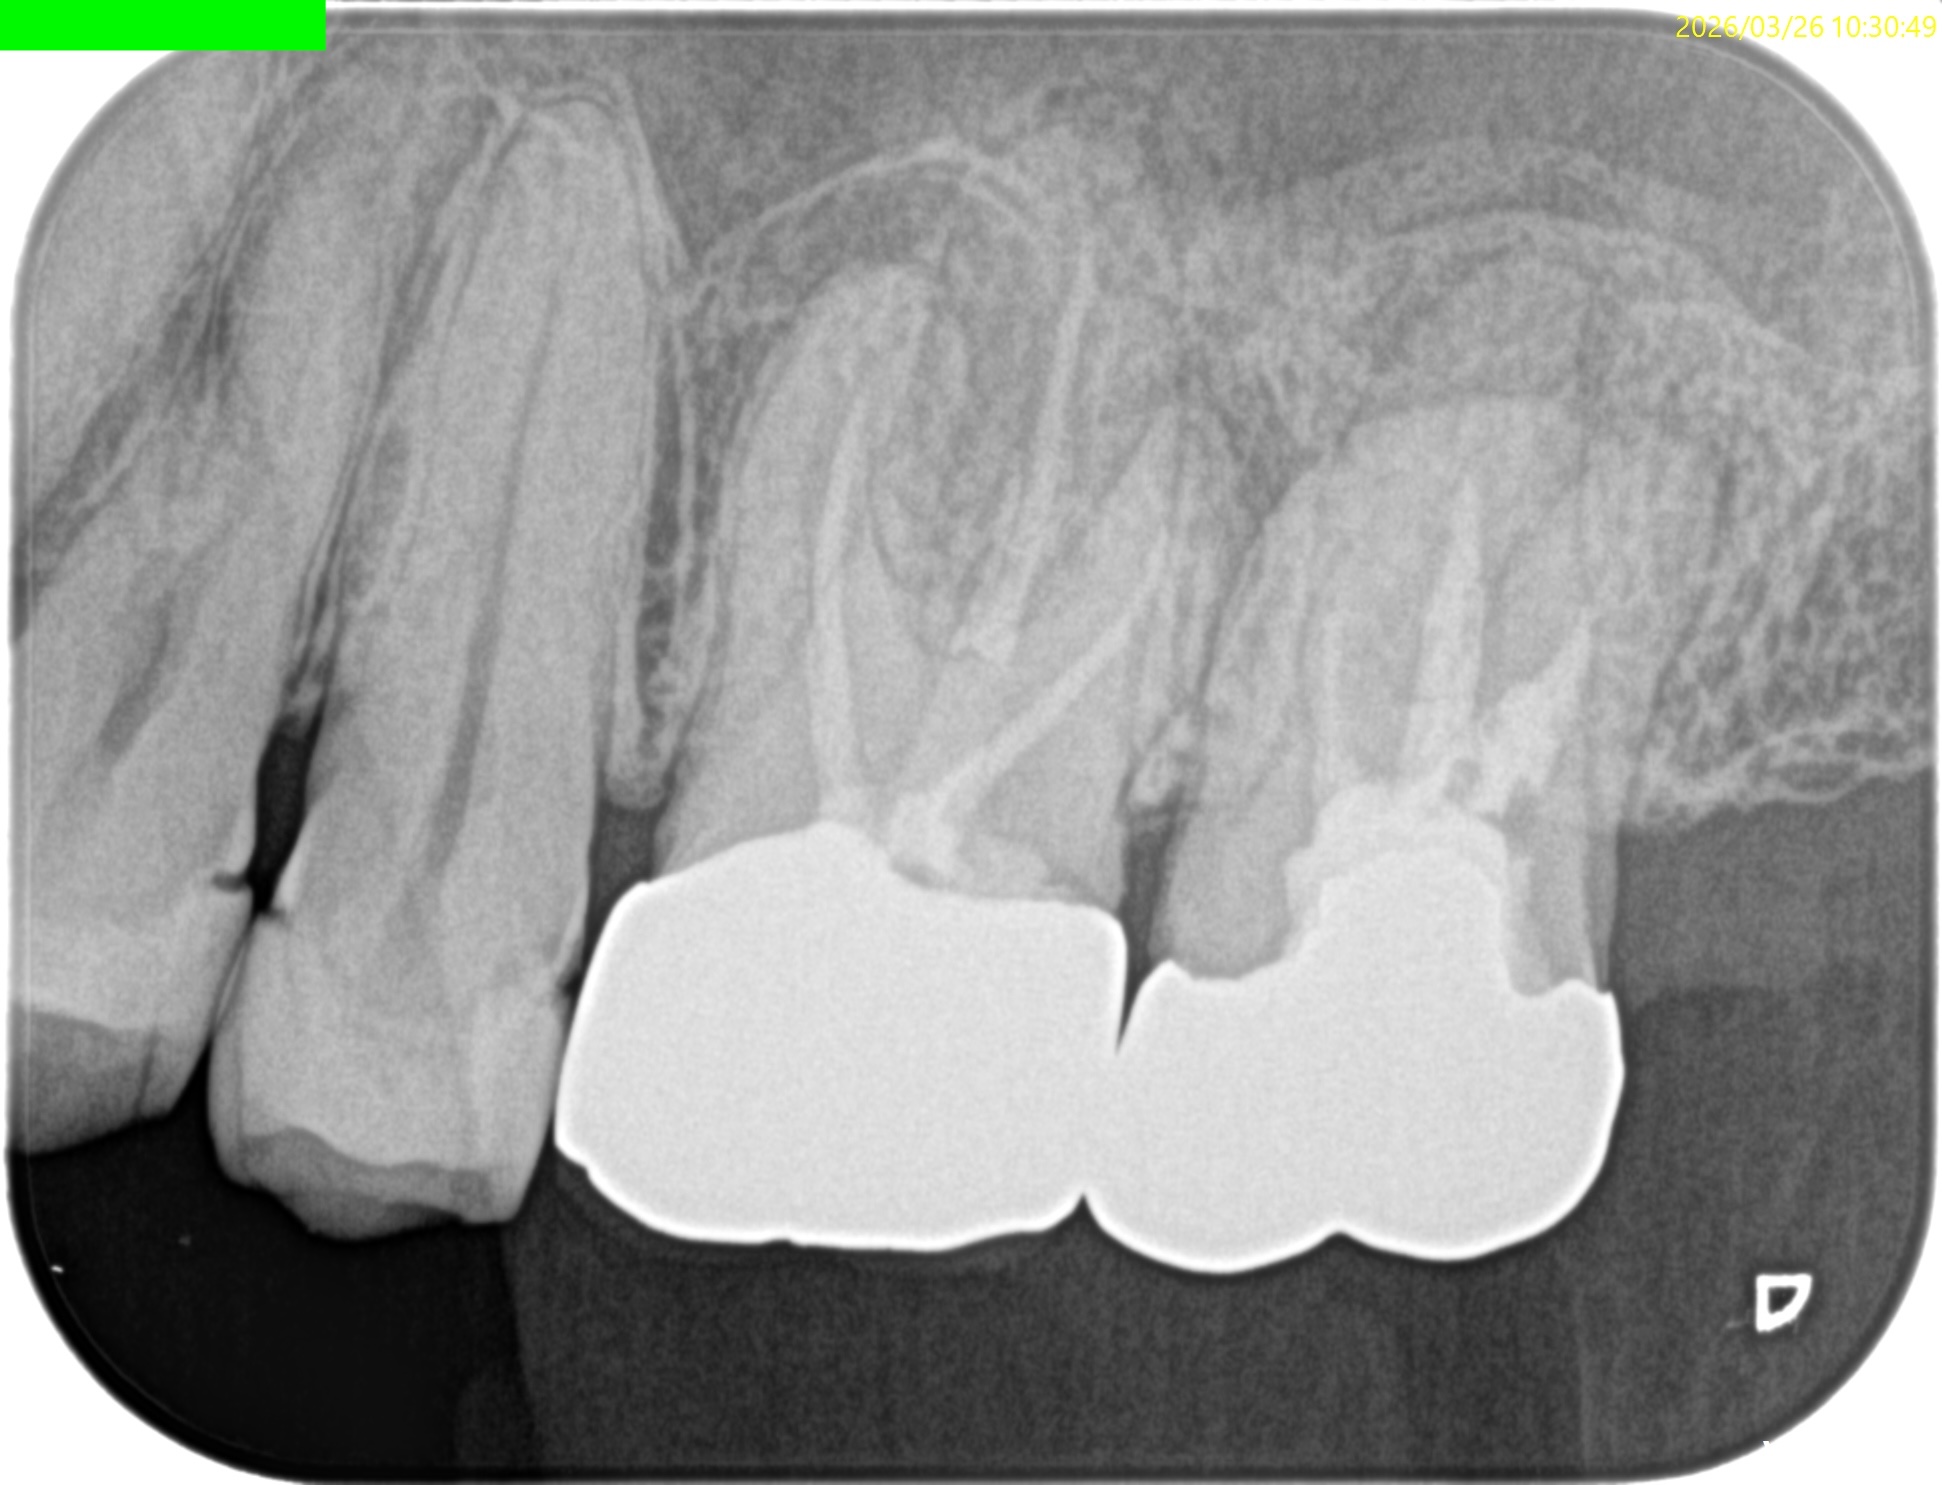

まず第2大臼歯から。

MB

MB2

DB

P

複数根管があるのはMBであるが、

これらの絵だけで合流しているか?否か?がわかるだろうか?

またMB2は見つかるだろうか?